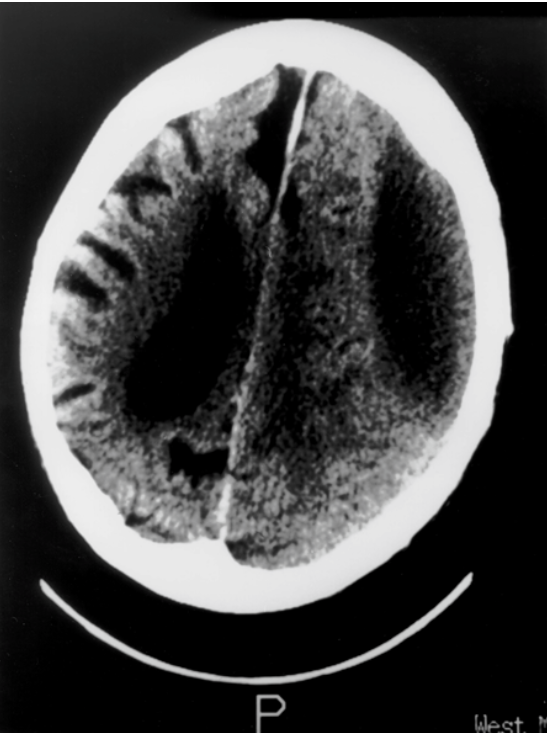

Examine the CT scan provided, identify any abnormalities that are present and suggest a diagnosis

Anterior left cerebral bleed - damage to subdural bridging veins

Subdural haemorrhage = symptom build up over few days, caused by trauma

Bleed around left frontal lobe and Broca’s Area

Lemon shape = signifies blood is within the dural area of the brain (blood pushes and shifts the brain) VS banana shape = epidural bleed as blood between skull and dura = blood seeps around the edge of the skull forming a banana shape